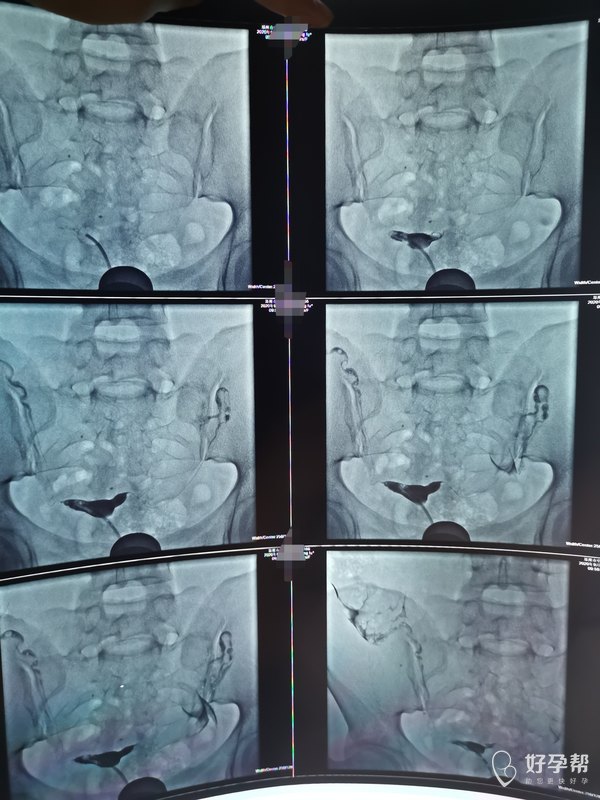

想问医生我这输卵管伞端上举是不是很严重是不是

对,你的输卵管上举很严重,一般输卵管伞端开口在子宫左右两旁,去拾取卵子,现在输卵管太高,拿不到卵子,就不能精子卵子结合受孕,如果年龄偏大不建议做手术,直接试管性价比更高